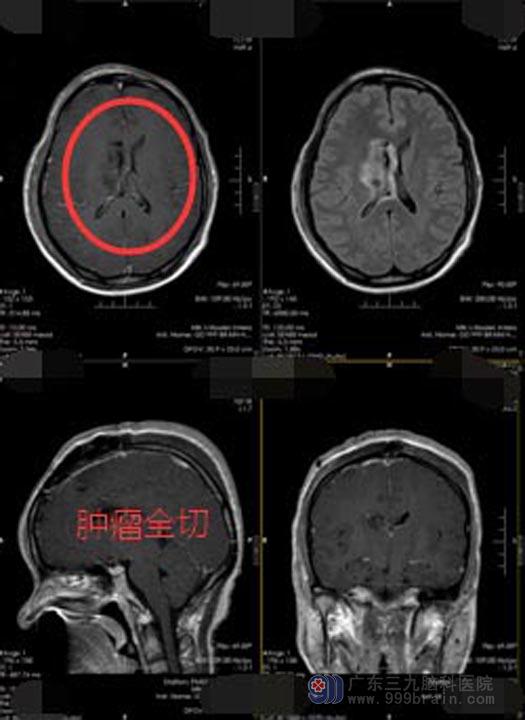

广东三九脑科医院行头颅MR检查提示:右侧侧脑室占位性病变,考虑为中枢神经细胞瘤可能性大。中枢神经细胞瘤对放疗敏感,直接手术风险极大,为减少手术风险,经多学科讨论后,决定先放疗再手术。

一周的放疗结束后,由医院副院长、神经外五科主任鲁明主刀行“右侧侧脑室神经细胞肿瘤切除术”,术中见肿瘤呈灰白色,质软,血供丰富,显微镜下将肿瘤分块全部切除。术后病理提示:不典型中枢神经细胞瘤,WHO II级。术后已解除病症,林小姐恢复良好,已经出院。